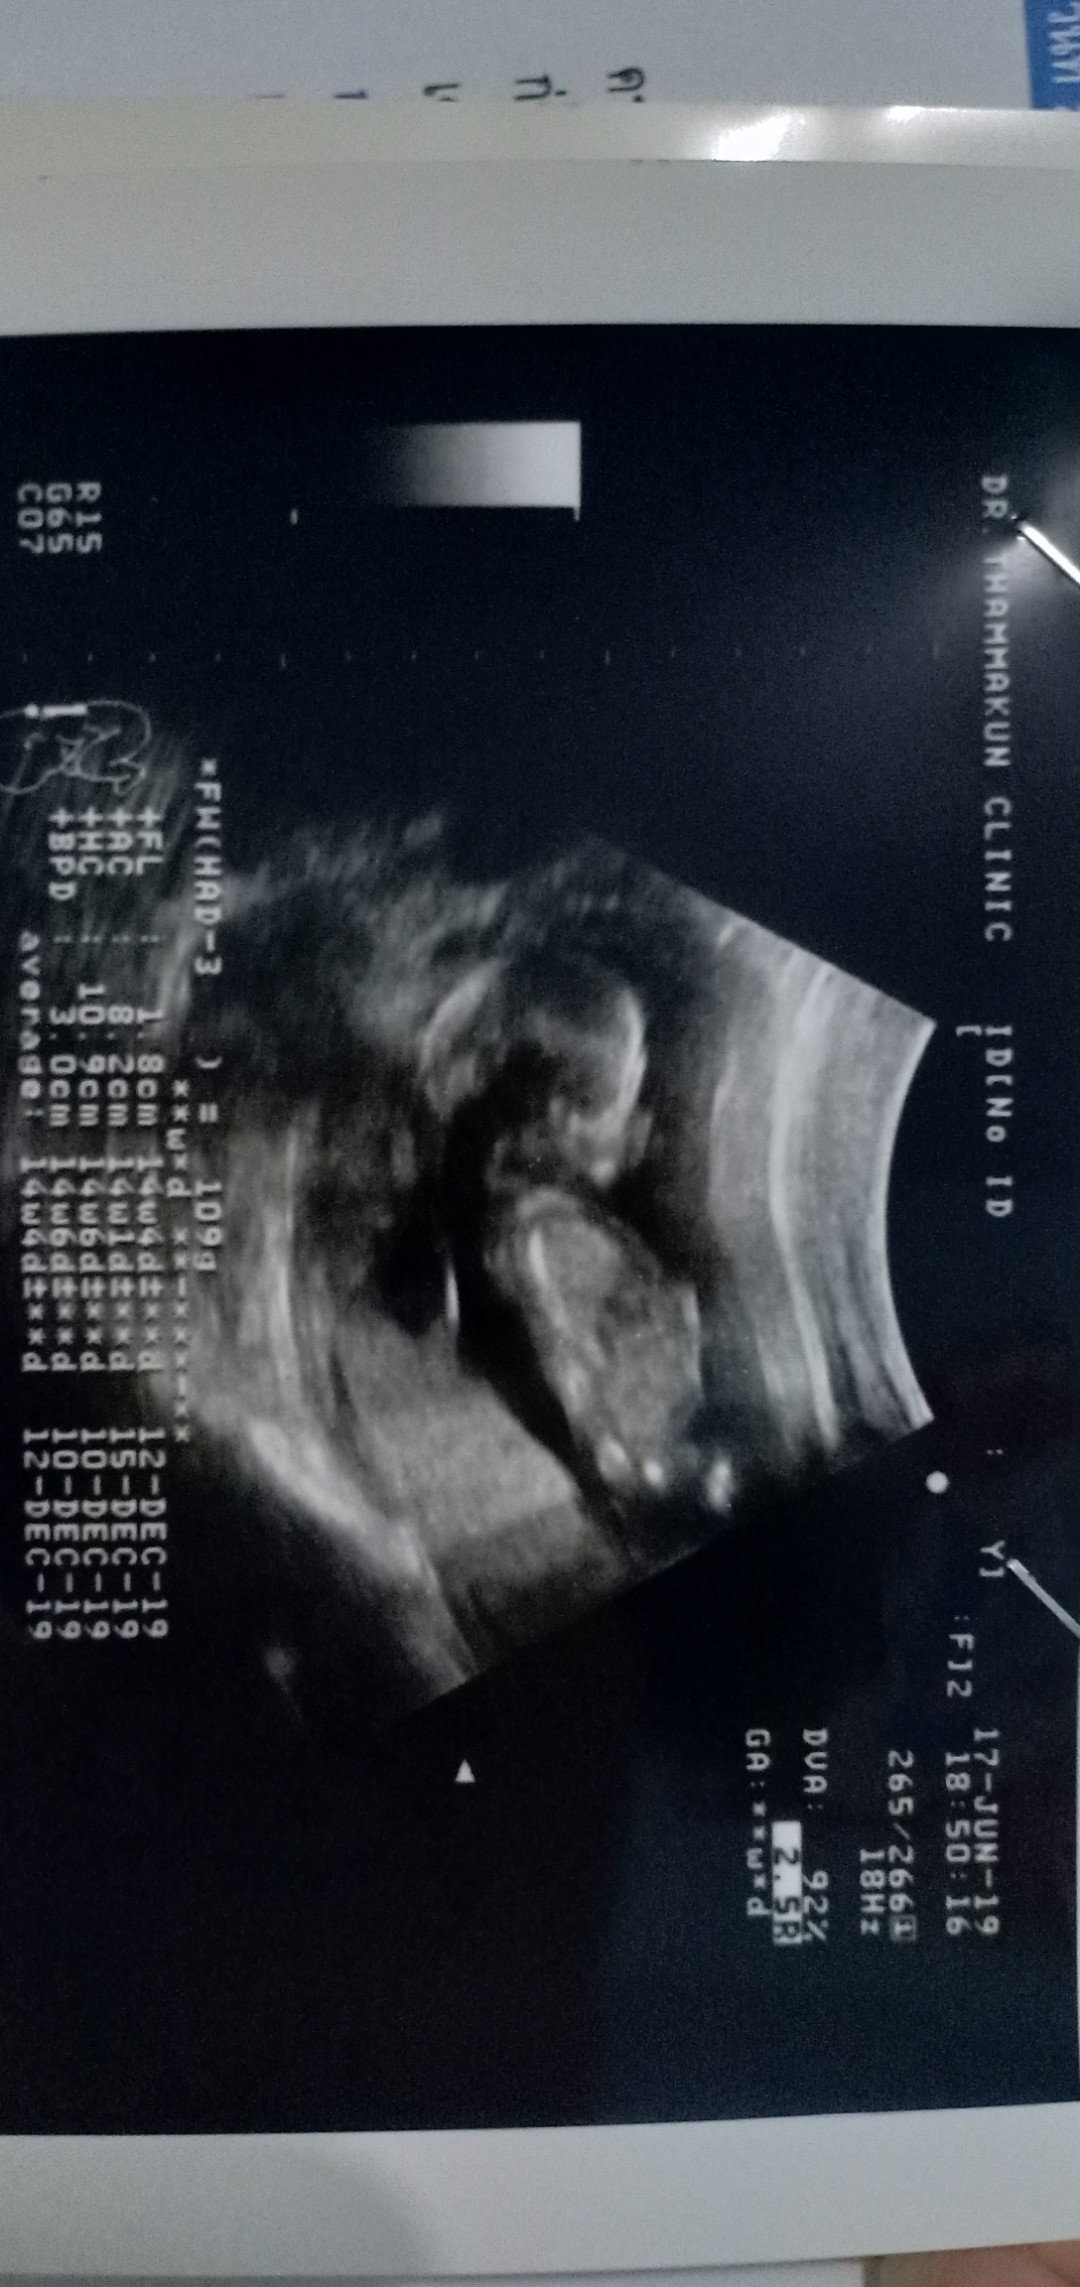

ซาวตอน13w ปัจจุบัน18wและค่ะ